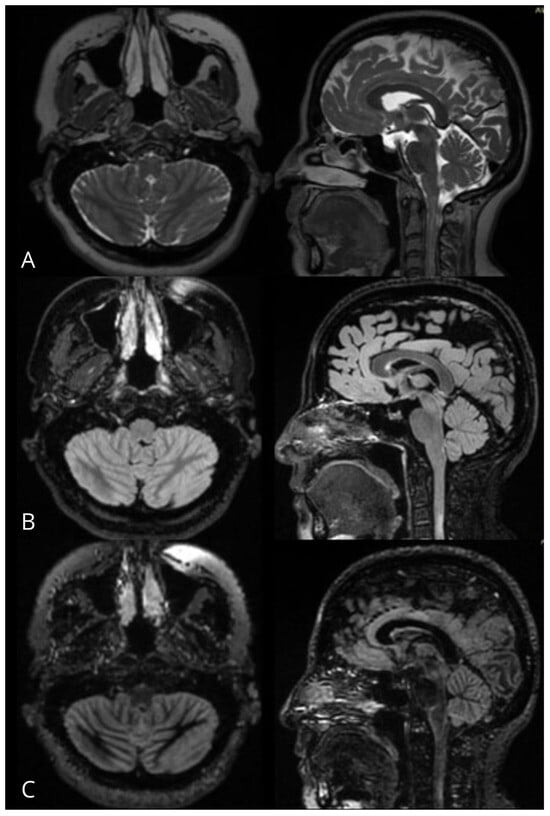

No statistically significant differences were found when comparing the degree of visualization in the different sequences between the group of patients with MS and the group with ND-CNSD (3D FSE Cube T2WI p = 0.286, 3D FSE Cube FLAIR p = 0.208, 3D DIR p = 0.307) (Figure 1) (Table 2).

Figure 1. MRI of a control group patient. (A) 3D FSE Cube T2WI, (B) 3D FSE Cube FLAIR, (C) 3D DIR in axial (left), sagittal (center), and coronal (right) planes, demonstrating the area postrema (circles) as a linear hyperintense zone on the dorsomedial surface of the medulla oblongata, adhering to the ventral angle of the floor of the fourth ventricle at the level of the obex.